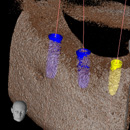

サージカルガイド

サージカルガイドは、インプラントの手術の際にあごの骨にドリリングする工程で、深さや位置を細かくガイドしてくれるツールです。

サージカルガイドを使うことで、歯科医師が事前にコンピューター上で綿密なシミュレーションを行って決めた人工歯根の埋入位置を、実際の治療で再現することが可能となります。